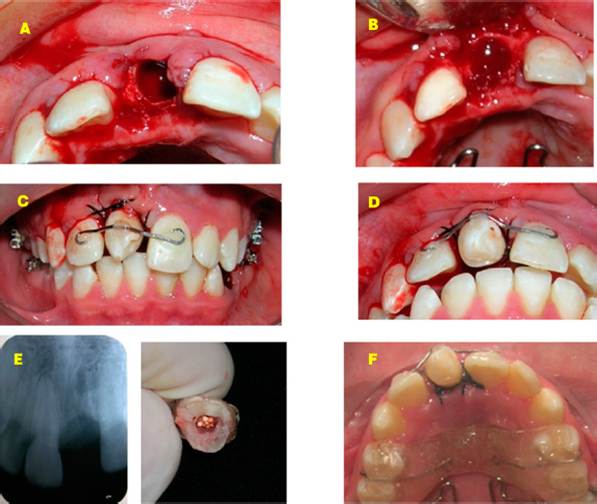

En la primera fase del tratamiento se realizó la colocación de bandas en los primeros molares superiores, dispositivo de anclaje y levantamiento de mordida con placa de acrílico para evitar el contacto oclusal. Posteriormente se procedió a la extracción del incisivo central superior derecho, siguiendo el protocolo de extracción del primer premolar inferior izquierdo, preparación del sitio quirúrgico, y el proceso de trasplante dental y ferulización durante cuatro semanas (Figura 3). En la segunda fase de trabajo se colocaron los brackets con prescripción Roth 0.022" Ovation de la marca GAC©. Primero se colocaron en la arcada inferior para disminuir la inclinación de los incisivos y mejorar la posición de los dientes mientras se realizaba la reparación y cicatrización del tejido peri implantar del diente auto trasplantado (Figura 4).

Figura 3 Primera fase de tratamiento. A-B. Preparación del nicho receptor. C-D. Fijación del diente trasplantado en el sitio del central maxilar. E. Radiografía dentoalveolar post extracción. F. Uso de placa de acrílico para favorecer el levantamiento de la oclusión.